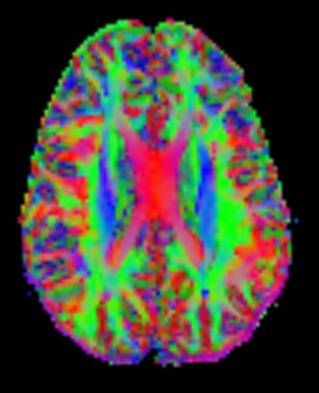

This additional information is difficult to represent on 2D grey-scaled images. To overcome this problem a color code is introduced . Basic colors can tell the observer how the fibers are oriented in a 3D-coordinate system: This is termed an "anisotropic map." Our software encodes the colors in this way:

- Red indicates directions in the X axis: right to left or left to right.

- Green indicates directions in the Y axis: posterior to anterior or from anterior to posterior.

- Blue indicates directions in the Z axis: foot-to-head direction or vice versa.

Notice that the technique is unable to discriminate the "positive" or "negative" direction in the same axis.

Color coded fractional anisotropy map. Pixels are now displayed in colors to reveal the predominant direction of the diffusion tensor. Green shows fibers oriented anterior-to-posterior or posterior-to-anterior. Red shows fibers oriented right-to-left or left-to-right (e.g.: corpus callosum). Blue shows fibers oriented head-to-foot or vice versa (e.g.: the pyramidal tracts in the corona radiata, lateral to the corpus callosum).